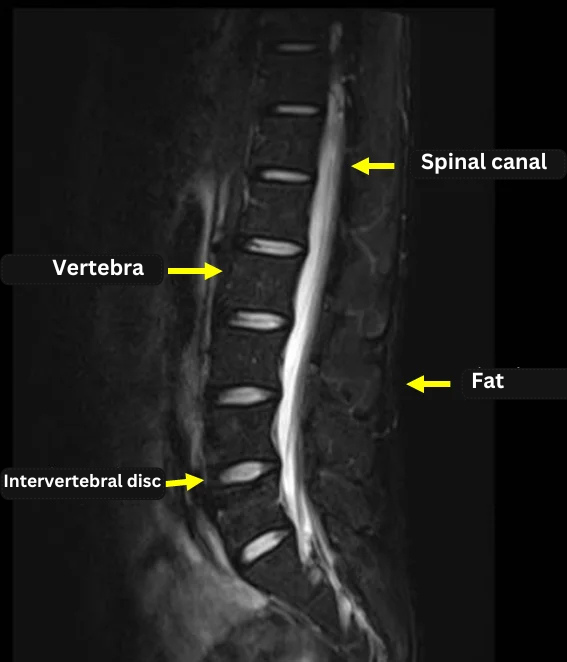

By examining the images below, you can see how the contrast changes between sequences.

(All three images were taken in the sagittal plane.)

T2 Imaging: Spinal fluid (CSF) within the spinal canal appears bright (white), making it ideal for visualizing the spinal cord and nerves.